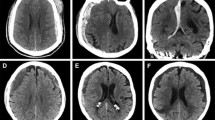

Imaging is key to make the diagnosis and establish a treatment plan. Head computed tomography (CT) is the fastest modality to determine presence, size and acuity of a SDH, and presence and size of midline shift (MLS). Immediate laboratory work up must include PT, PTT, INR, and platelet count. General treatment considerations include the assessment for need of mechanical ventilation, correction of a coagulopathy and treatment of seizures. Any patient with a confirmed or suspected acute SDH is at risk of rapid deterioration and should have immediate neurosurgical consultation to decide for surgical or nonsurgical management.

Urgent need for surgical evacuation of a SDH is largely influenced by neurologic examination, acuity of the hemorrhage, imaging characteristics, and presence of mass effect or elevated intracranial pressure. When patients with acute SDH present with other associated intracranial injuries, such as contusions or diffuse axonal injury, a GCS of <15 at presentation is not necessarily an indication to operate. Further aspects for triage into operative and nonoperative management are age of the patient, advanced directives, and the probability of a favorable outcome. No randomized trials have compared surgery with conservative management for patients with acute SDH. Multiple studies have shown that patients with acute SDH >10 mm in initial hematoma thickness or >5 mm of MLS are likely to require operative intervention [23, 72, 73].

Limited observational data suggest that stable patients with isolated small acute SDH can be managed nonoperatively [72, 73]. Nonoperative management in an intensive care unit is also recommended for neurologically stable patients with an acute traumatic SDH with clot thickness <10 mm, midline shift <5 mm, without pupillary abnormalities, and no intracranial hypertension on ICP monitoring when presenting with a GCS score <9 [8]. Outcomes were reported to be at least as safe for those patients compared with surgical treatment when ICP and clinical condition remained stable [23]. If triaged to nonsurgical treatment, close observation, ICP monitoring if indicated, and serial brain imaging are important, as hematoma enlargement and neurologic deterioration requiring surgery may occur later on. For patients with traumatic head injury, serial follow-up head CT scans should be obtained during the first 36 hours after injury, as there is a high incidence of clot expansion during this interval [81]. The individual timing of the first follow-up scan depends on the initial presentation and findings.

Risk factors for hematoma expansion and eventual requirement of surgery include lower GCS score on presentation, additional intracranial injuries on CT scan such as mass effect, intraventricular hemorrhage, and epidural hematoma [81], as well as a combination of neurologic worsening and MLS >5 mm [82], or neurologic deterioration in the setting of initial clot thickness >10 mm [72].